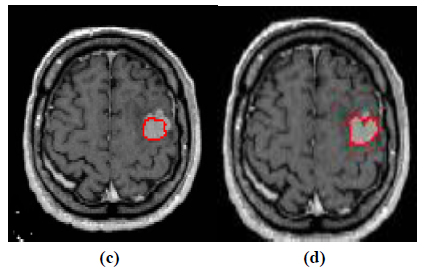

The experiment is conducted using brain web and Digital Imaging Communications in Medicine (DICOM) database [27, 28]. These database consists of T2 weighted MR images of sizes with tumor history. Pre-processing of an original MR image is an important step before applying the segmentation algorithms. In this case, the original MR image is pre-processed by applying median filter. Median filter removes salt and pepper noise which is very common in MR images of the brain. After removing the noise, wavelet transform is applied for multiresolution analysis to enhance the features of the image. Then, spatial FCM technique is applied to the multiresolution image. This technique minimizes search area to a very small region by creating cluster number k parameter for termination and max iteration values. Finally, these tumor clusters are segmented by level set evolution algorithm [29-39]. The following experimental results demonstrate the segmentation process used in the proposed methodology. In this experiment, two MR images having tumor in different locations of the image were selected to test the proposed segmentation algorithm. In Fig. (3), the original image and contour initialization for MR image 1 is shown. The contour evolution and final segmentation are depicted in Fig. (4). Similarly, Fig. (5) shows the original MR image 2 and the initial contour position. As the iteration values increases, the contour evolves towards the tumor boundary.

The qualitative results of the proposed method show that, the convergence of the contour towards the object boundary is very accurate and rate of convergence of the contour using level sets method is better than the traditional active contour models. The quantitative analysis is also carried out for the proposed technique using various performance measures.